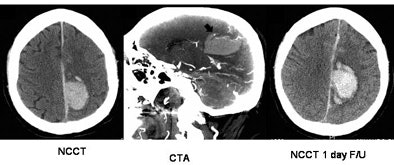

![]() |

| Top, a patient with CTA spot sign (+VE) and hematoma expansion; bottom, a patient with CTA spot sign (-VE) and no expansion. Patients presenting with the spot sign at CT were more than eight times as likely to have hematoma expansion. Images courtesy of Dr. Richard Aviv. |